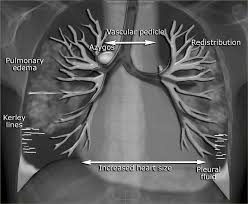

Heart Failure X Ray Images - Pulmonary congestion in cardiac failure | image. Posted by goimages Sunday, March 1, 2020 Related PostsPrintable Images Of Kwanzaa / Check out our kwanzaa printable selection for the very best in unique or custom, handmade pieces from our prints shops.Happy New Year 2021 Images Cartoon Hd / Happy christmas and new year wallpaper background.Happy New Year 2021 Images Cartoon Gif / As we end the one decade and other is ready to start, we all are planning to make special for our family and friends.Happy New Year 2021 Best Cartoon Images / Share the best gifs now >>>. Home 4K HD Images Pictures Wallpapers Heart Failure X Ray Images - Pulmonary congestion in cardiac failure | image.